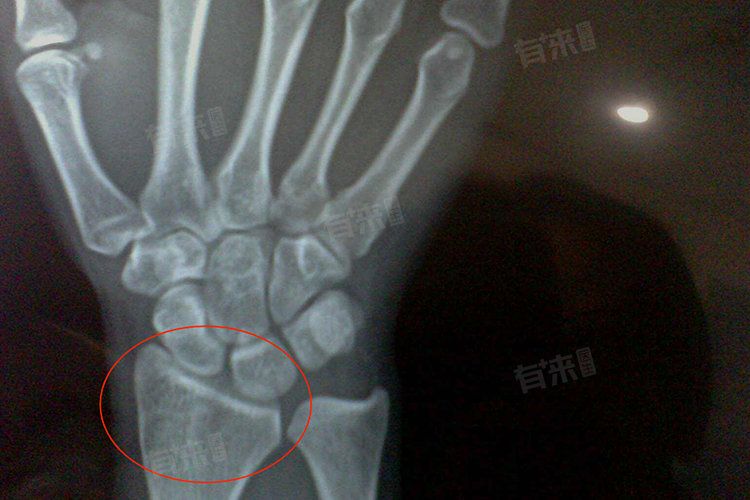

5、影像学检查确认:最准确判断骨骺闭合的方法是影像学检查,到骨科进行X线检查,医生通过观察手腕、膝盖等部位骨骼影像,能清晰看到骨骺线状态。若骨骺线变窄甚至消失,就可确诊骨骺闭合。这是判断骨骺闭合的金标准,为进一步决策提供精准依据。